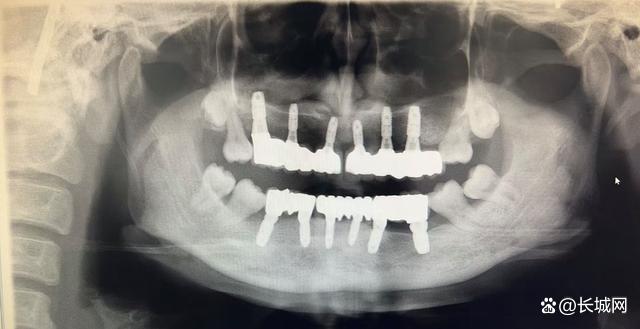

接诊的口腔二病区主任张特检查发现,让朱女士30岁的年龄却有80岁的牙齿的罪魁祸首是侵袭性牙周炎。待其牙周状况稳定后,为她做了全口种植修复。3个月后,朱女士戴上了“新牙”,颜值大大提升,绽放出自信笑容。12月18日,朱女士复诊后对诊疗效果很满意,对张特主任团队表示感谢。

△全口种植修复后